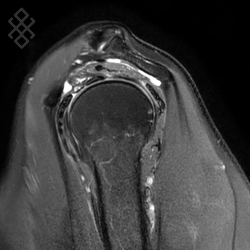

IRM de l’Épaule